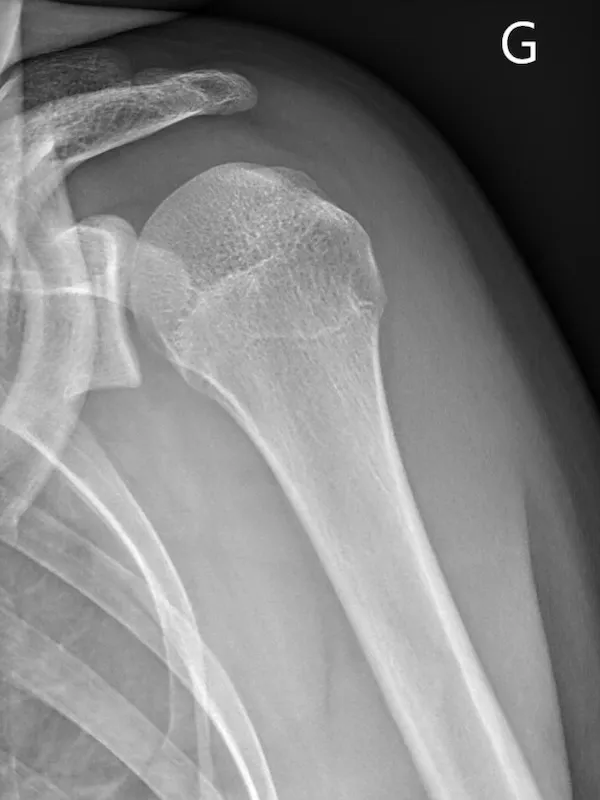

Quels examens complémentaires réaliser ?

- Radiographies — bilan de débrouillage, recherche de lésions osseuses associées

- Arthroscanner — examen de référence : quantifie précisément la perte osseuse glénoïdienne, évalue le labrum, la capsule et la coiffe

- IRM — en complément si lésion tendineuse associée suspectée